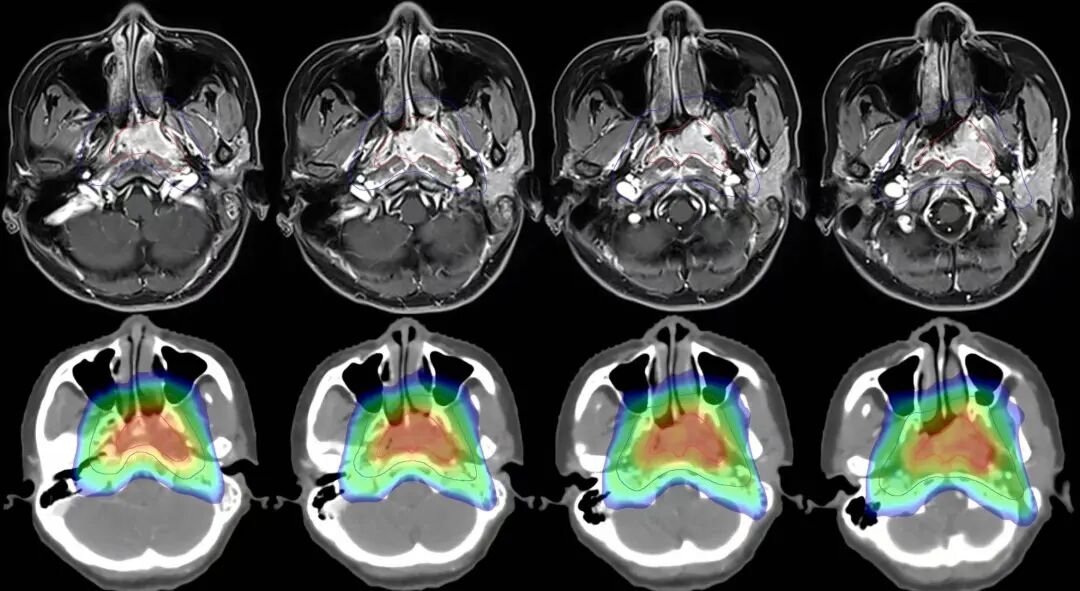

注解:360°容積弧形調(diào)強(qiáng)放療,高劑量集中在腫瘤區(qū)域,同時(shí)降低皮膚劑量。

圖注:上排紅線內(nèi)為腫瘤照射靶區(qū)。下排為劑量分布圖,可見中心區(qū)高劑量照射,周邊劑量快速跌落,形成銳利的集束聚焦照射,周圍重要器官得到良好保護(hù)。